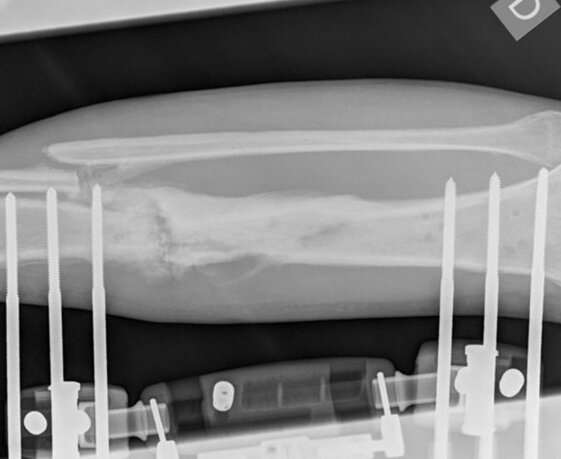

Radiological control one month after the start of therapy. The fistula closed. The X-ray examination demonstrates the formation of callus, prevalent on the side opposite the insertion of the external fixators and the signs of consolidation of the focus of pseudarthrosis.